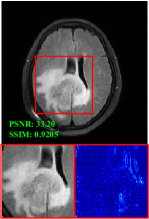

Figure 5 provides the qualitative comparison of the various methods on the four datasets at a scale of 4. The top, second, third, and bottom rows are the SR results under the FastMRI, clinical brain, clinical tumor and clinical pelvic datasets, respectively. The red boxes indicate the zoom-in region of complicated anatomical structures along with their corresponding error maps. Note that the brighter textures in the error maps, the lower the quality of the reconstructed images. As can be seen, compared to methods based on Transformers and CNNs, diffusion-based methods like DisC-Diff and DiffMSR (Ours) are capable of reconstructing high-realistic images with promising reconstruction metric scores (PSNR and SSIM). Nevertheless, while DisC-Diff can reconstruct high-precision MR images, it does not preserve the structure present in the original HR images, introducing some additional information that can affect medical diagnosis. In contrast, our method combines DM and PLWformer, which can preserve the original image’s structure while restoring high-frequency information.

In this section, we present more visual qualitative comparisons. Figures 8, 9, 10, and 11 show the reconstruction results of each method in FastMRI, clinical brain, clinical tumor, and clinical pelvic, respectively. As can be seen, although DisC-Diff can reconstruct MR images with high-frequency information, it fails to preserve the structure and content of the original Target HR image effectively, resulting in image distortion. In contrast, our proposed DiffMSR can restore high-frequency information while preserving the structure of the original HR image, indicating the effectiveness of the joint use of DM and PLWformer.